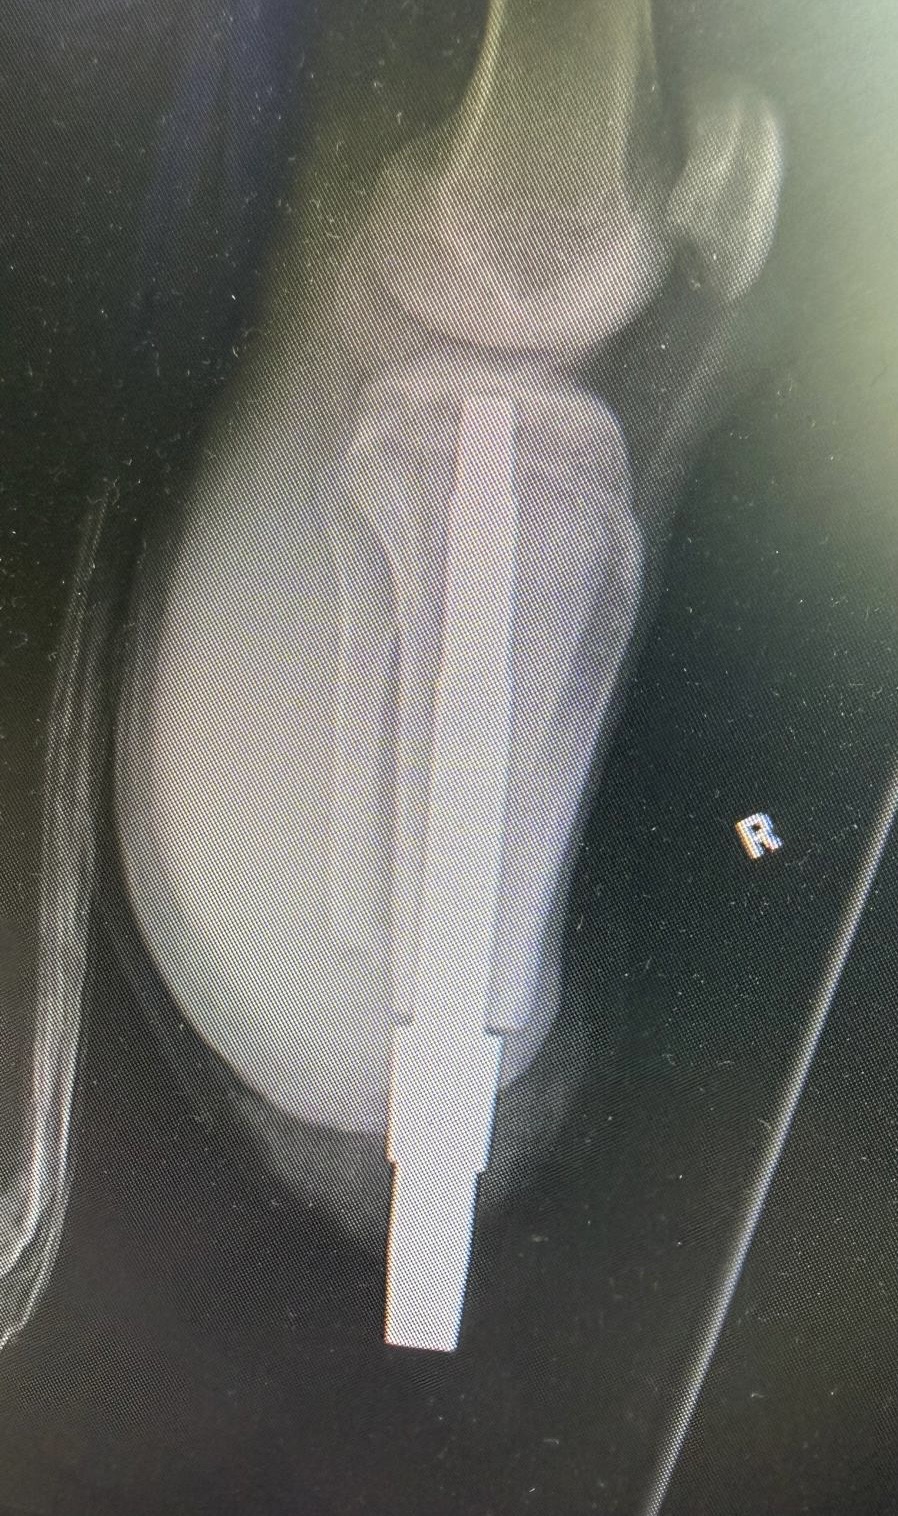

W Klinice Traumatologii i Ortopedii WIM-PIB przeprowadzono innowacyjny i rzadko wykonywany zabieg jednoczasowej osseointegracji obu podudzi u 19-letniego pacjenta po amputacji urazowej. To ważny krok naprzód w nowoczesnym leczeniu osób po amputacjach kończyn dolnych.

Osseointegracja polega na trwałym połączeniu implantu z kością, co umożliwia bezpośrednie mocowanie protezy bez konieczności stosowania tradycyjnego leja protezowego. Rozwiązanie to zapewnia pacjentom większy komfort użytkowania, lepszą kontrolę ruchu oraz wyraźną poprawę jakości życia. Przeprowadzona operacja była szczególnie wymagająca, ponieważ objęła obie kończyny jednocześnie. Jednoczasowe wykonanie zabiegu niesie jednak istotne korzyści – pozwala uniknąć drugiej hospitalizacji i kolejnego znieczulenia ogólnego, skraca całkowity czas leczenia oraz umożliwia prowadzenie symetrycznej rehabilitacji obu kończyn już od początku procesu usprawniania. Dzięki temu pacjent ma szansę szybciej powrócić do samodzielnego funkcjonowania.

Tego typu zabiegi należą do rzadkości i są wykonywane jedynie w nielicznych, wysoko wyspecjalizowanych ośrodkach. Operacje osseointegracji stanowią ważny krok w kierunku przywracania sprawności i niezależności osobom, które doświadczyły ciężkich urazów.